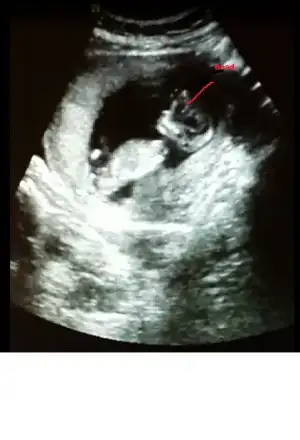

bak buda bacak arası. ama video çekmiştik sanki pipi var gibi geldi bana. acaba kordon mu o? çok kalındı zaten keşke videoyu gönderebilsem sana :).. bu arada yorumun için çok teşekkür ederim canım:KK68:

Canım kızda da erkekte de bu haftalarda çıkıntı oluyor sadece kızın çıkıntılı karşıya bakıyor erkeğin yukarı doğru senin o pipi gibi gösterdiğin karşıya bakıyor kız gibi yani yinede yanılma payı vardır mutlaka